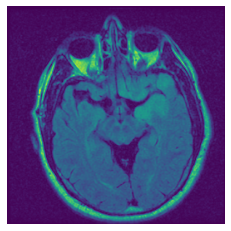

In figure 3, we present qualitative examples of different masking strategies. It is observed that, unlike context prediction and restoration, our method tends to propose targeted masks like the tumor regions or regions with abnormalities and avoids masking less helpful regions. However, it should be noted that Intelligent-Masking does not necessarily mask the tumor regions but considers all areas of interest that results in better feature learning. Examples of other masking samples are provided in supplementary materials. Furthermore, in medical images, unlike natural scenes, the structures are very local with imbalanced information throughout an image. Therefore, random masking strategies as shown in Fig 3 operate ineffectively by masking non-informative regions.

(a) Original

(b) Intelligent-Masking

(c) Context Prediction

(d) Context Restoration

Figure 2: Qualitative examples of compared method’s strategies for masking